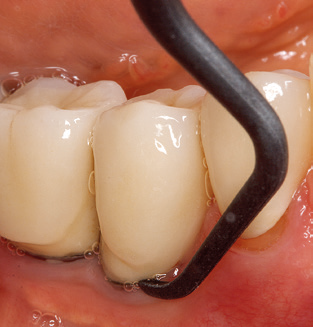

Fig. 4: Flexible probes with millimetre markings are recommended for the probing of dental implants (e.g. Colorvue Kit PCV11KIT6, Hu­Friedy). – Fig. 5a and b: A straight working tip (1P, W&H Dentalwerk Bürmoos GmbH) is a suitable instrument for use on all natural teeth. – Fig. 6: Curved working tips (3Pr/3Pl, W&H Dentalwerk Bürmoos GmbH) lend themselves to the processing of difficult-to-reach areas of the tooth and root surfaces (e.g. furcations). – Fig. 7: The tapered, hexagonal implant cleaning tip (1I, W&H Dentalwerk Bürmoos GmbH) permits atraumatic and efficient cleaning of the crown and abutment surfaces. – Fig. 8: Titanium and carbon curettes are suitable instruments for the manual cleaning of the implant surfaces.

The current working concept for SPT

Updating the patient’s medical history is an important aspect of SPT and should occur at least once per year. It helps the dental team to identify and document any new risk factors. Especially when a patient is treated over many years, it is important to establish whether patient-specific and general health risk factors have changed. This primarily concerns a heightened risk as a result of diabetes, but other general conditions (cardiovascular disease and neoplasia) can also produce a modified risk profile as a result of the treatment performed and medication administered. Accordingly, updating the medical history as part of SPT is very important, as a modified risk profile may trigger the need to adapt the treatment interval. In the next step, it is important to afford the diagnostics due attention. Whilst instruments are a central aspect of SPT, findings and their documentation must never be neglected. The periodontological findings are essential for a good diagnosis; increases in the pocket depths and the BOP index are clear indicators of advancing periodontal and peri-implant disease. As such, the team should not shy away from probing implants too, with the aim of gathering the requisite data. At the same time, it is important to use periodontal probes with millimetre markings. Metallic probes have already been used for determining pocket depths around natural teeth for decades. In the case of implants, the challenge of recording correct and reproducible pockets depths is even greater. As the discrepancy between the implant diameter and the contour of the superstructure regularly results in overcontouring of the superstructure, flexible probes which still feature millimetre markings are a sensible solution for measuring pocket depths around implants (e.g., Colorvue Kit PCV11KIT6, Hu­Friedy; Fig. 4).